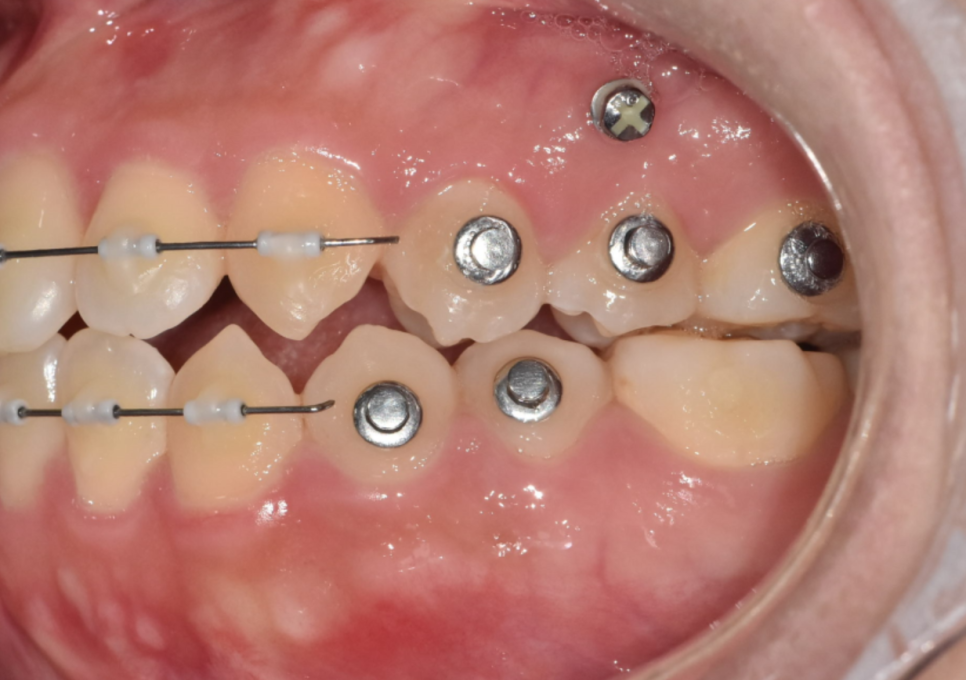

250304

피어싱할 때 느낌과 비슷하다 설명드리는데

대개 다음날부터는 일상 회복이 가능합니다.

그렇지만 시술 당일 통증을 줄이기 위해서는

자극적이고 딱딱한 음식보다는

부드럽고 잇몸에 무리가 안가는 음식 섭취를 하는 것이 좋습니다